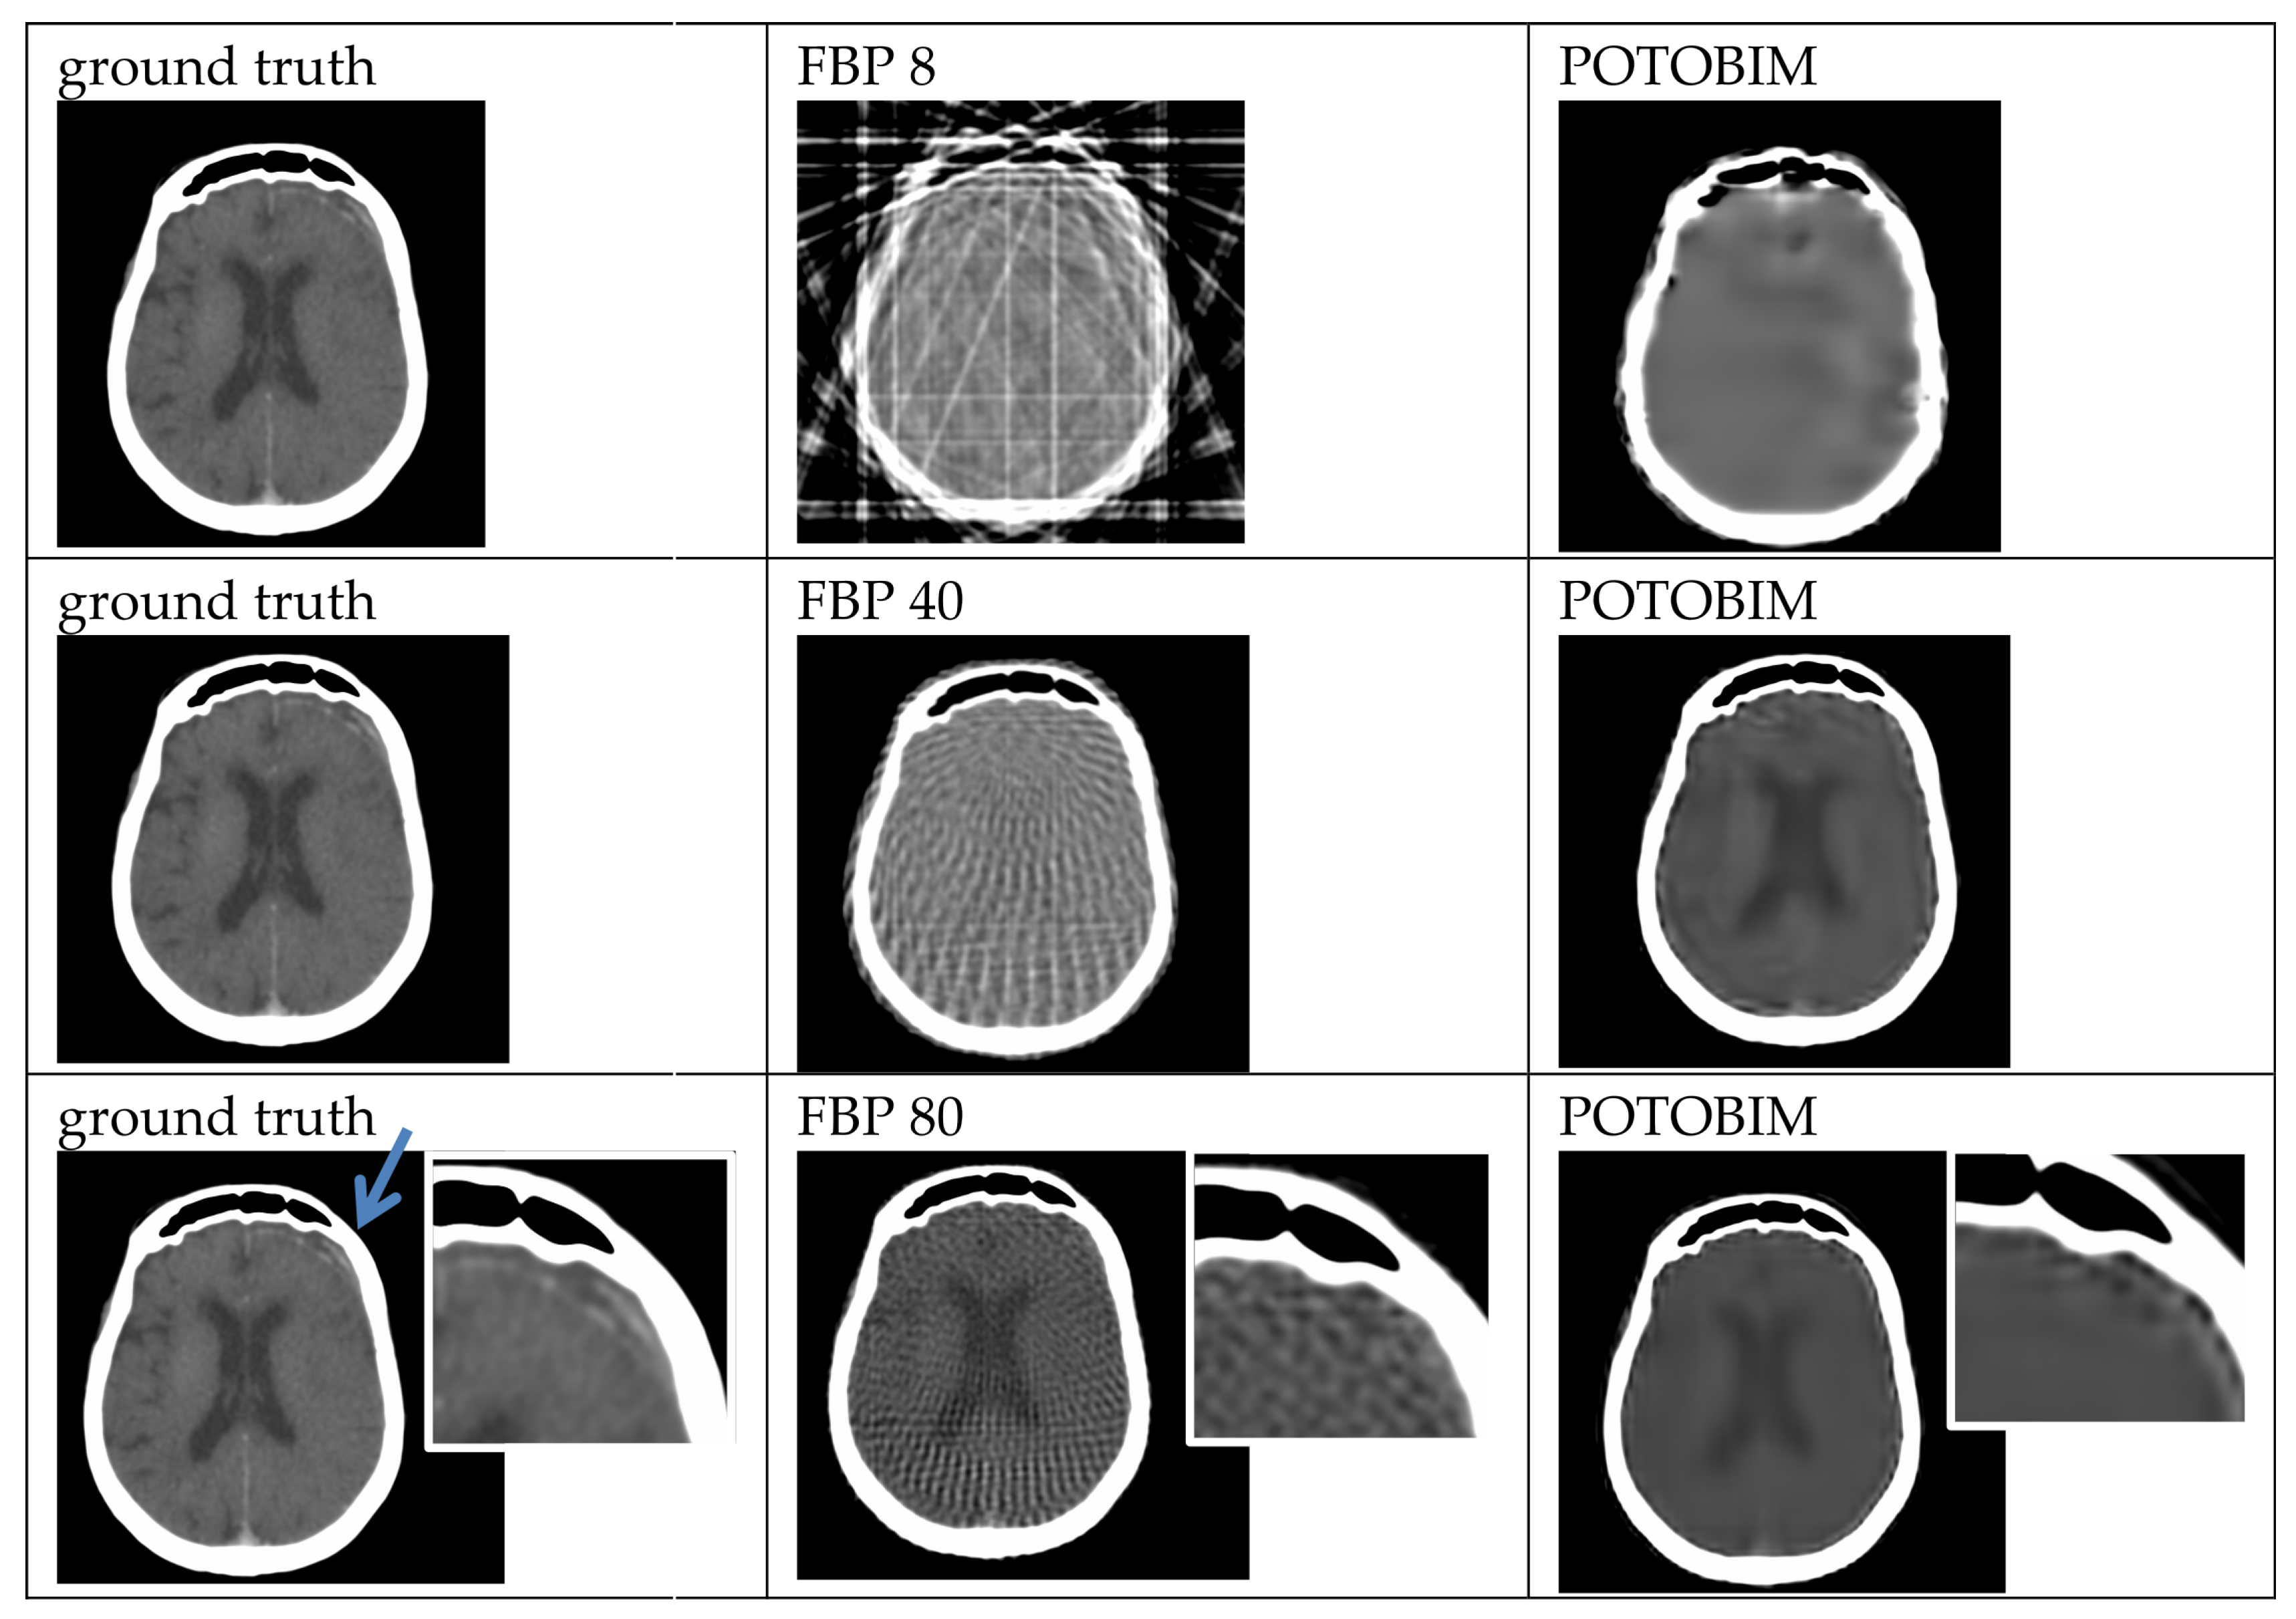

2.3. Sparse-View Reconstruction

3. Results

3.1. Visual Grading

3.2. Quantitative Evaluation